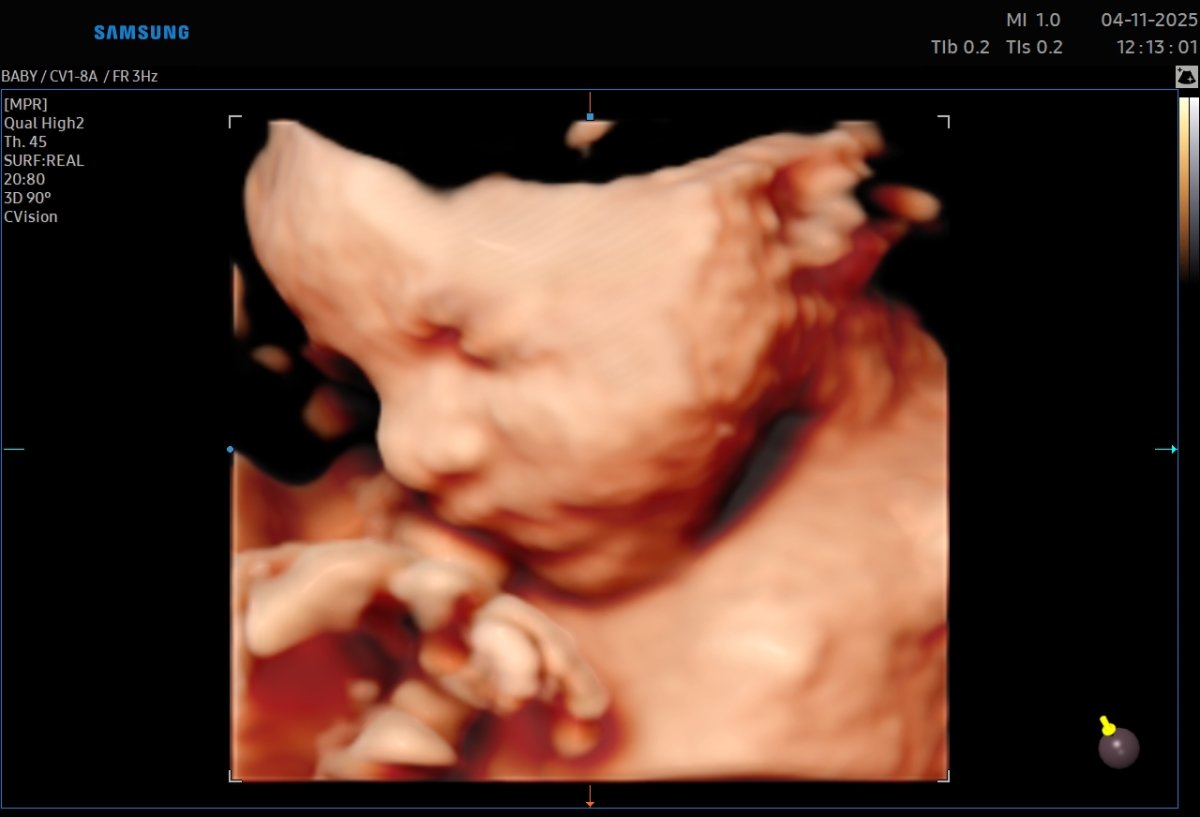

Gallerie de photos